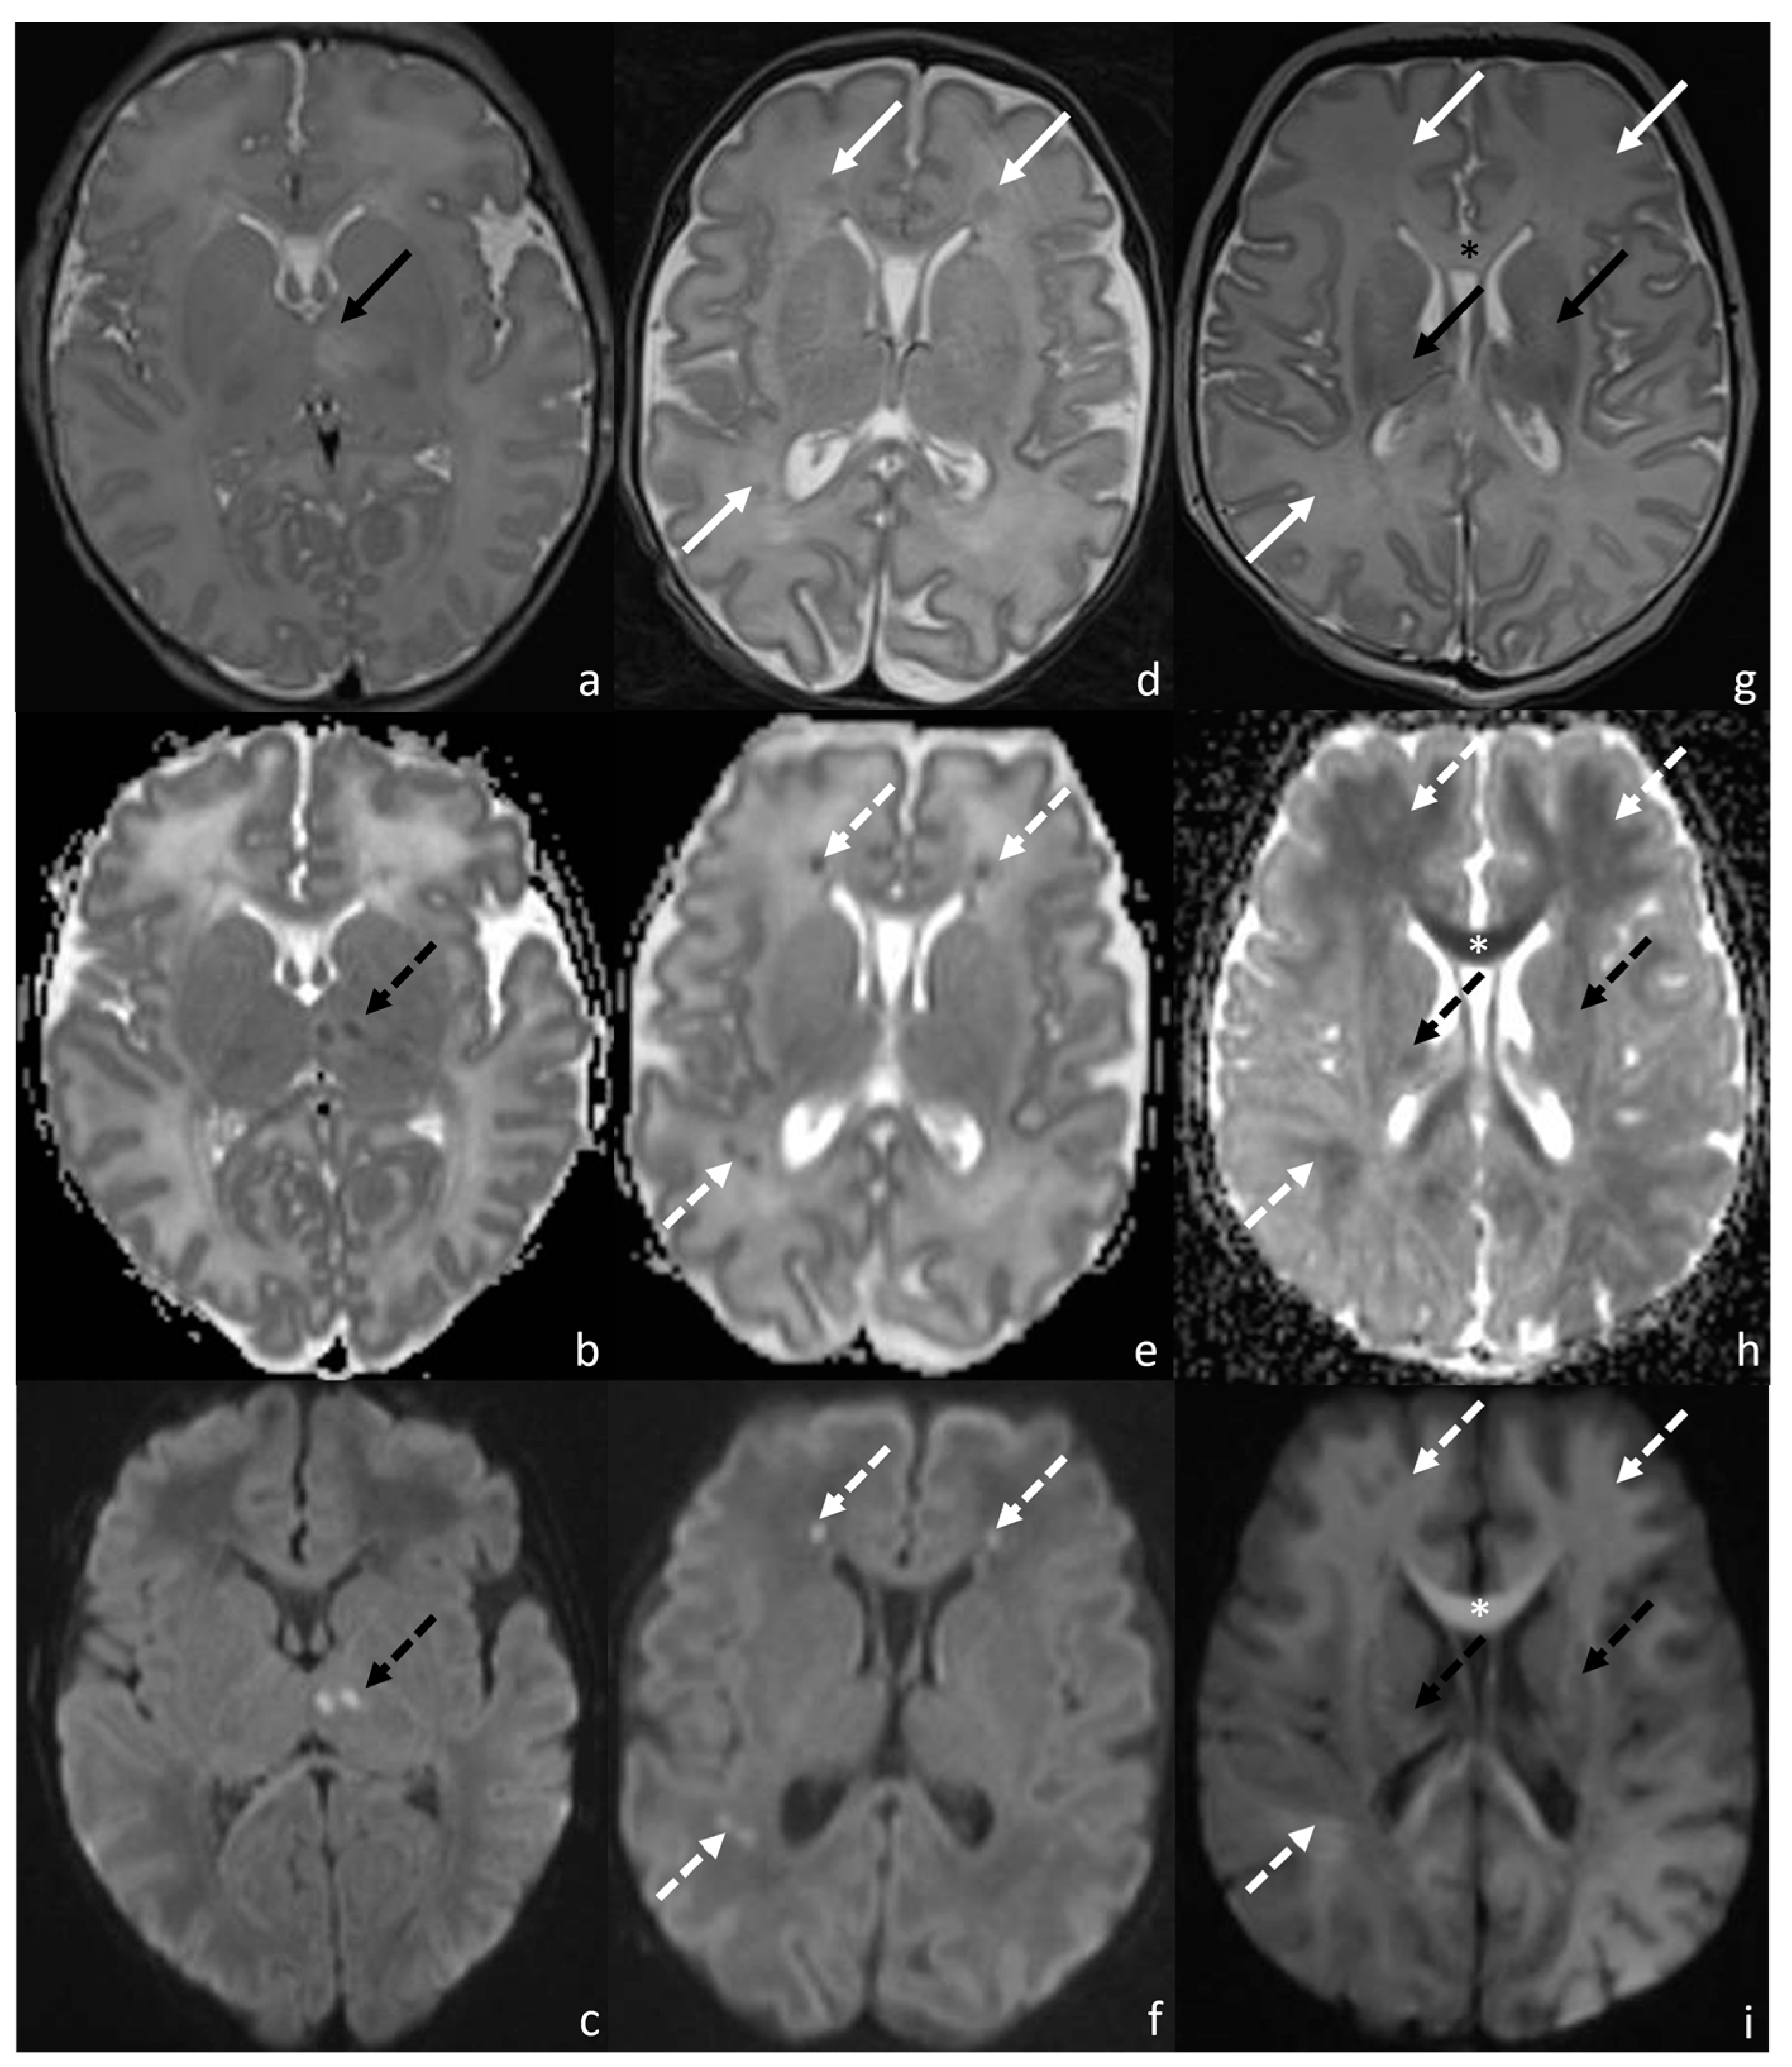

1. Introduction

2. Materials and Methods

2.2. MRI Acquisition

2.3. Radiological Evaluation

2.3.1. Van Rooij Score

2.3.2. Measurement of ADC Values